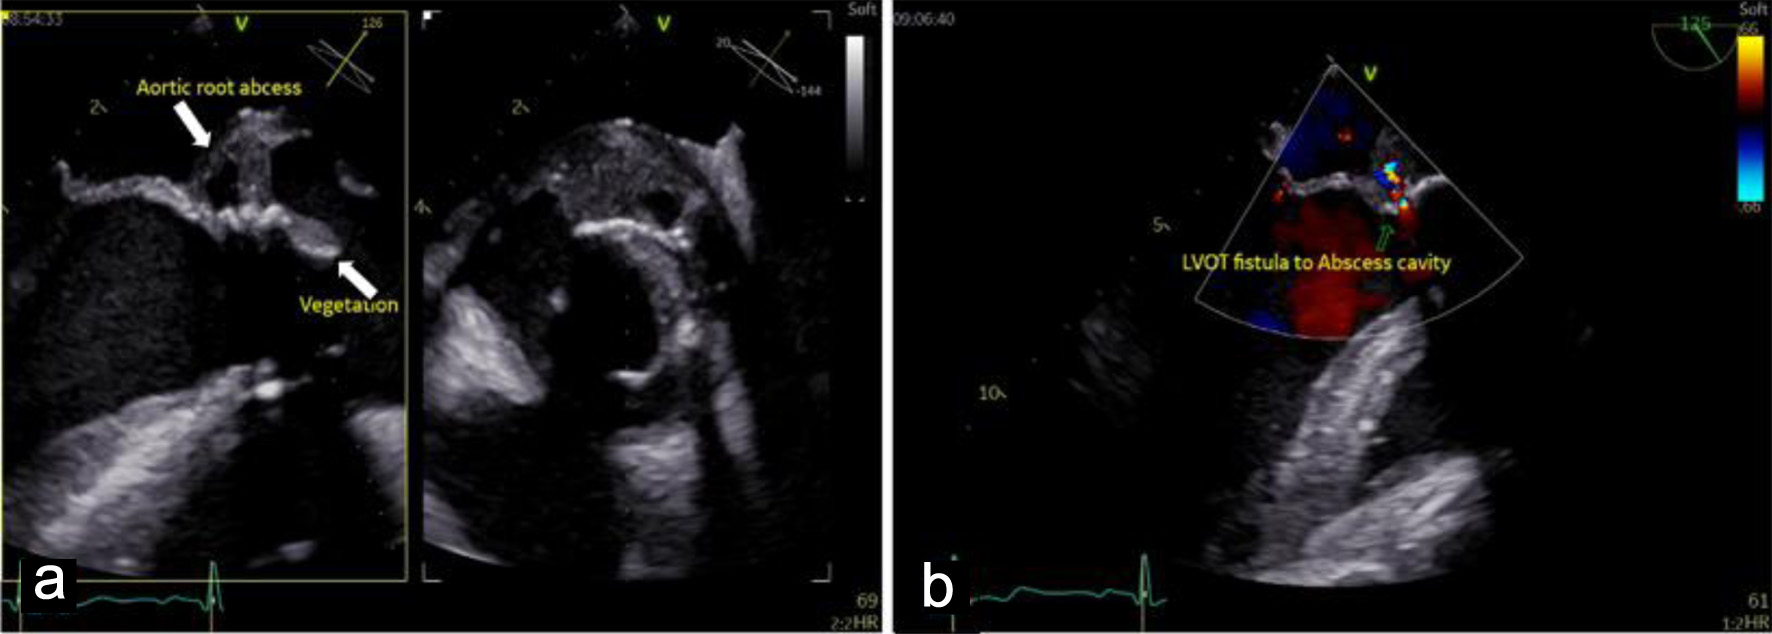

Cardiac evaluation was initiated with transthoracic echocardiography (TTE), which identified a mobile, pedunculated vegetation measuring approximately 3 × 6 mm attached to the prosthetic aortic valve suture line. The vegetation was associated with mild aortic regurgitation, while overall prosthetic valve function remained preserved. Left ventricular systolic function was maintained, with an estimated ejection fraction of 54%, and no signs of heart failure or significant ventricular dilation were observed. To further characterize the extent of valvular and periannular involvement, TEE was subsequently performed. TEE confirmed the presence of the prosthetic-valve vegetation and revealed a paravalvular aortic-root abscess (Fig. 2) extending into the sinuses of Valsalva and involving the mitral–aortic intervalvular fibrosa. These findings were indicative of advanced prosthetic-valve IE with periannular extension (Fig. 3), a condition traditionally associated with poor prognosis and strong indications for urgent surgical intervention.

Figure 2. Mid-esophageal view transesophageal echocardiogram (TEE) demonstrates: (a) pedunculated vegetation (lower arrow, measured 3 × 6 mm) on the bioprosthetic aortic valve cusp, and paravalvular aortic-root abscess (upper arrow), indicating advanced infective endocarditis. (b) Doppler echocardiogram shows left ventricular outflow tract (LVOT) fistula to the abscess cavity.